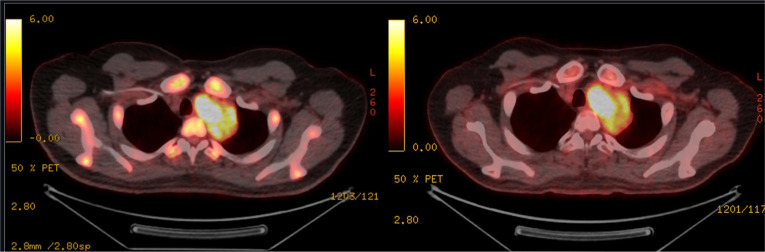

白血病肿块是血液恶性肿瘤患者的一种已知并发症。我们在此介绍一例新近确诊的 B 型急性淋巴细胞白血病(B-ALL)患者,该患者出现多个部位的髓外受累,包括前纵隔肿块。尽管接受了多剂细胞毒治疗,但肿块仍持续存在。在本报告中,我们总结了有关 B-ALL 纵隔肿块的文献,并说明白血病患者的此类肿块可能有令人惊讶的病因,与原发疾病无关。

Leukemic masses are a known complication in patients with hematologic malignancies. Here we present a case regarding a patient with recently diagnosed B-acute lymphoblastic leukemia (B-ALL) who presented with multiple sites of extramedullary involvement including an anterior mediastinal mass. This mass persisted despite multiple rounds of multiagent cytotoxic therapy. In this report, we summarize the literature regarding mediastinal masses in the setting of B-ALL and illustrate that such masses in patients with leukemias may have surprising etiology, separate from the primary disease.